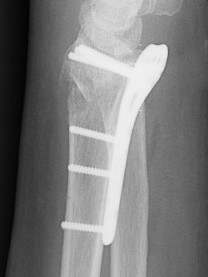

Undisplaced wrist fracture

- interrupts blood supply at a watershed area

- between 3 weeks and 3 months post injry